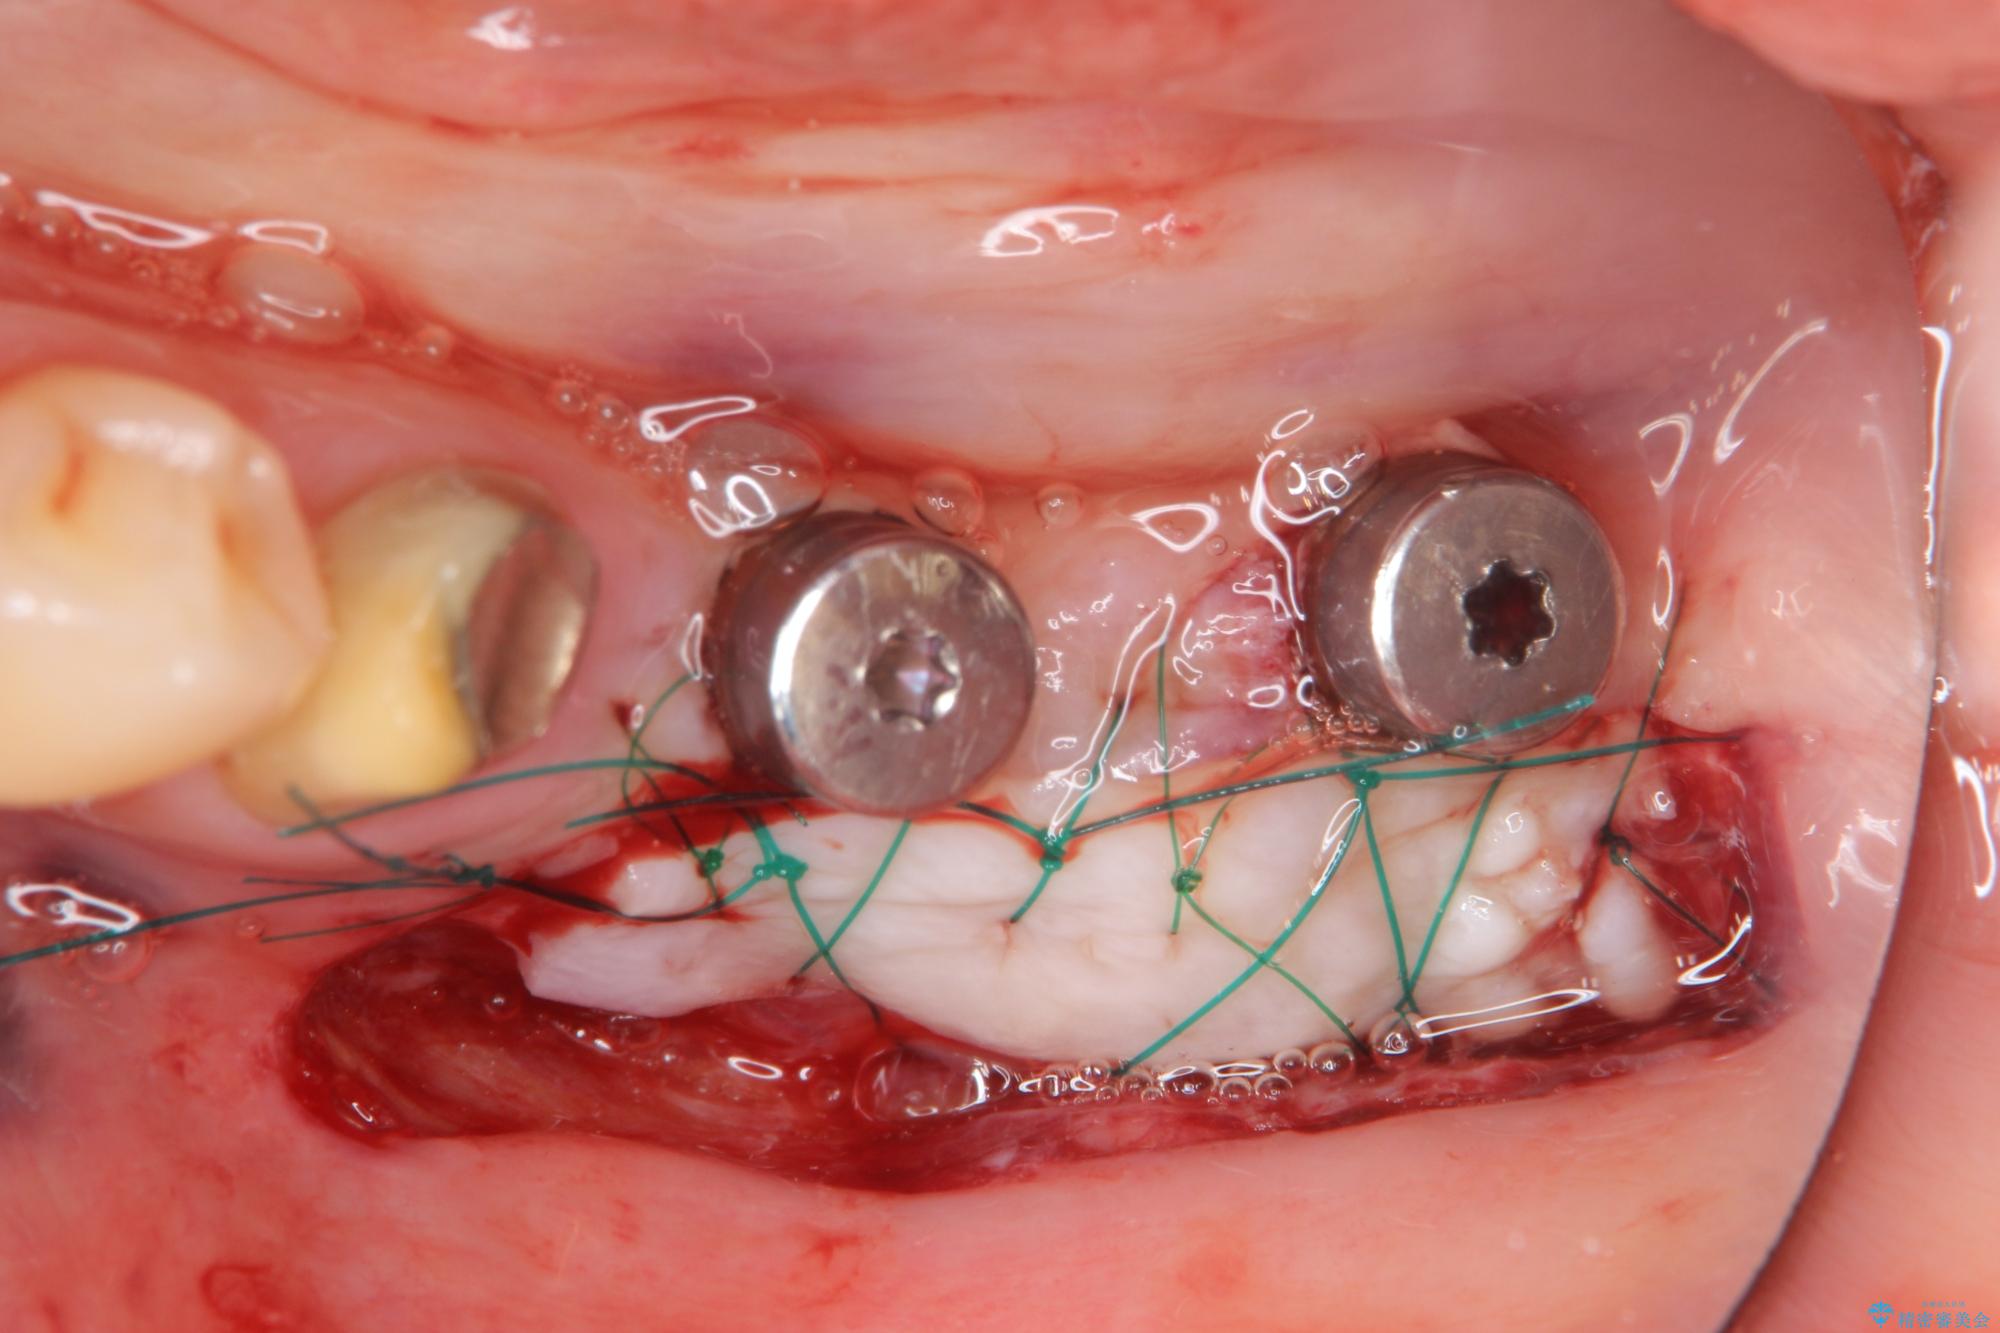

抜歯後、インプラントを用いて咬合機能を回復すると共に周囲に強固な角化歯肉を移植することによりより長期にわたり安定したインプラント周囲環境となるよう治療を計画します。

- 83.6万円(インプラント×2・アバットメント×2・クラウン×2)費用は治療当時の料金となります

インプラント周囲の角化歯肉が存在することにより、歯ブラシがしやすくなりインプラントにトラブルが起きる確率を減らしより長期的な予後を望むことができます。